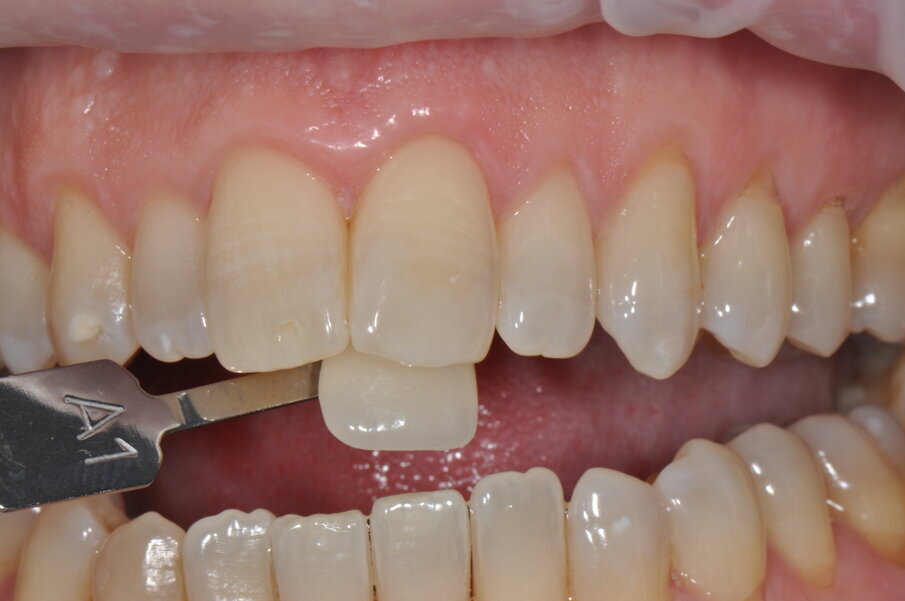

Fig. 9 - Colore post sbiancamento professionale utilizzando la scala “Vita” A2.

Fig. 10 - Colore finale utilizzando la scala “Vita” A1.